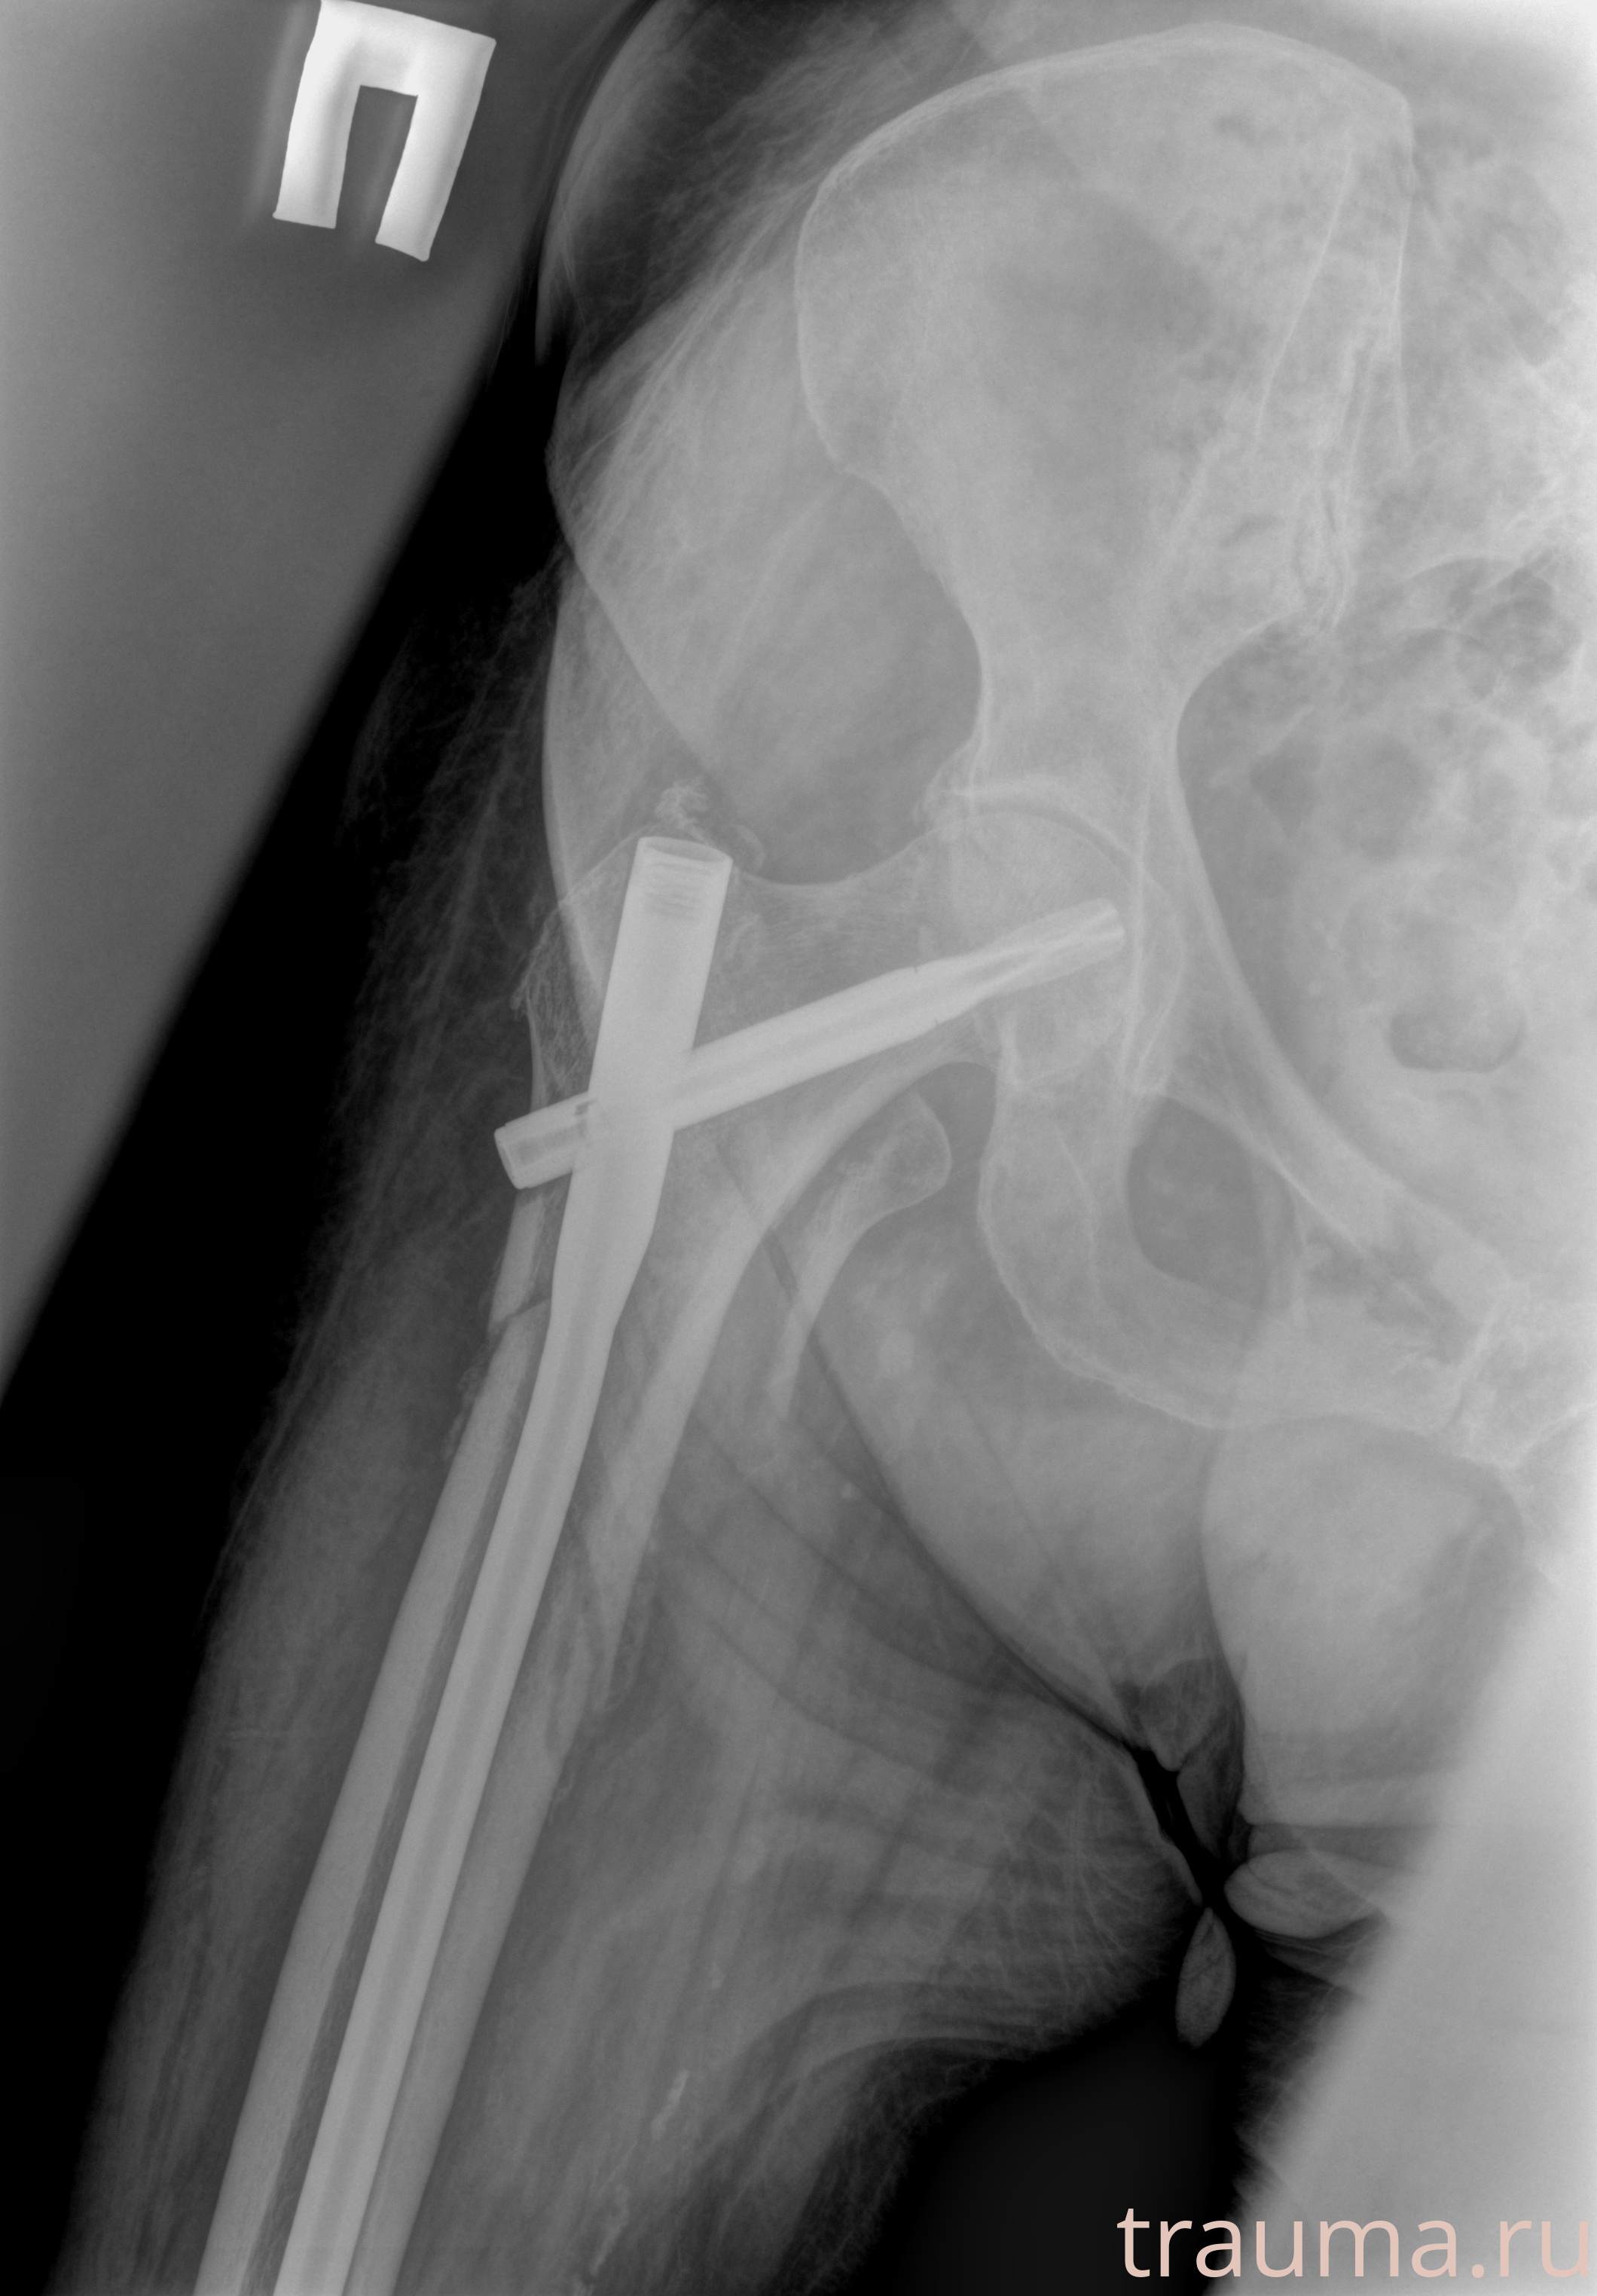

Рентген на дому: по вашему адресу приезжает врач-рентгенолог, травматолог-ортопед с мобильным рентгеновским аппаратом, проводит диагностику травмы или заболевания, делает необходимые рентгенограммы, дает рекомендации по дальнейшему лечению. Получить качественные снимки в домашних условиях возможно благодаря уникальной методике, разработанной МосРентген Центром для института  Склифосовского